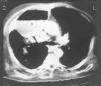

Un varónde 69 años con historia de hipertensión arterial yenfermedad pulmonar obstructiva crónica (EPOC) fue ingresadoen el hospital por agudización de su insuficienciarespiratoria crónica. Dos semanas más tarde,presentó oliguria progresiva, hiperuricemia e hiperkaliemiapor fracaso renal obstructivo secundario a un adenoma depróstata cuyo diagnóstico se desconocía. Porello, fue ingresado en nuestra unidad con cuadro deencefalopatía urémica y fracaso respiratorio,requiriendo intubación endotraqueal y ventilaciónmecánica. La primera radiografía torácica enla UCI mostró ausencia de hallazgos anormales. Tras elsondaje uretral, el fracaso renal se resolvió, y no fueronnecesarios procedimientos dialíticos. A las setenta y doshoras tras el ingreso en UCI, estando el paciente enventilación mecánica, presentó cuadro febrilcon temperatura de 38,5 ºC que se continuó con signosde shock séptico, precisando soporte hemodinámico condopamina y posteriormente noradrenalina. La radiografía detórax mostró un infiltrado en el lóbulosuperior derecho. En el aspirado traqueal se cultivóAcinetobacter baumannii (>106 ufc/ml),modificándose el tratamiento a imipenem y amicacina. En laradiografía se hizo evidente una progresión hacia lacavitación en el lóbulo pulmonar superior derecho. Latomografía axial computarizada (TAC) torácica (fig.1)mostró una gran colección líquida con gas anivel superior en el segmento anterior de dicho lóbulo, conconsolidación alveolar periférica por infiltradoneumónico. Las muestras recogidas por broncoscopia pusieronde manifiesto de nuevo el crecimiento significativo deAcinetobacter baumannii, no observándosecélulas neoplásicas, siendo el resultado negativopara la tinción de Zielh-Nielsen y el cultivo en medioLowenstein. Se procedió a drenaje percutáneo de lacavidad, con mejoría parcial del paciente, y el cultivo desu contenido confirmó Acinetobacter baumannii con lamisma sensibilidad a antimicrobianos que en las pruebas anteriores.No se cultivaron microorganismos anaerobios en el material delabsceso.

Fig. 1. Tomografía axial computarizada (TAC) detórax realizado a los diecinueve días de estancia enla unidad de cuidados intensivos (UCI) mostrando una grancolección líquida en el lóbulo pulmonarsuperior derecho con infiltrado neumónicoperiférico.